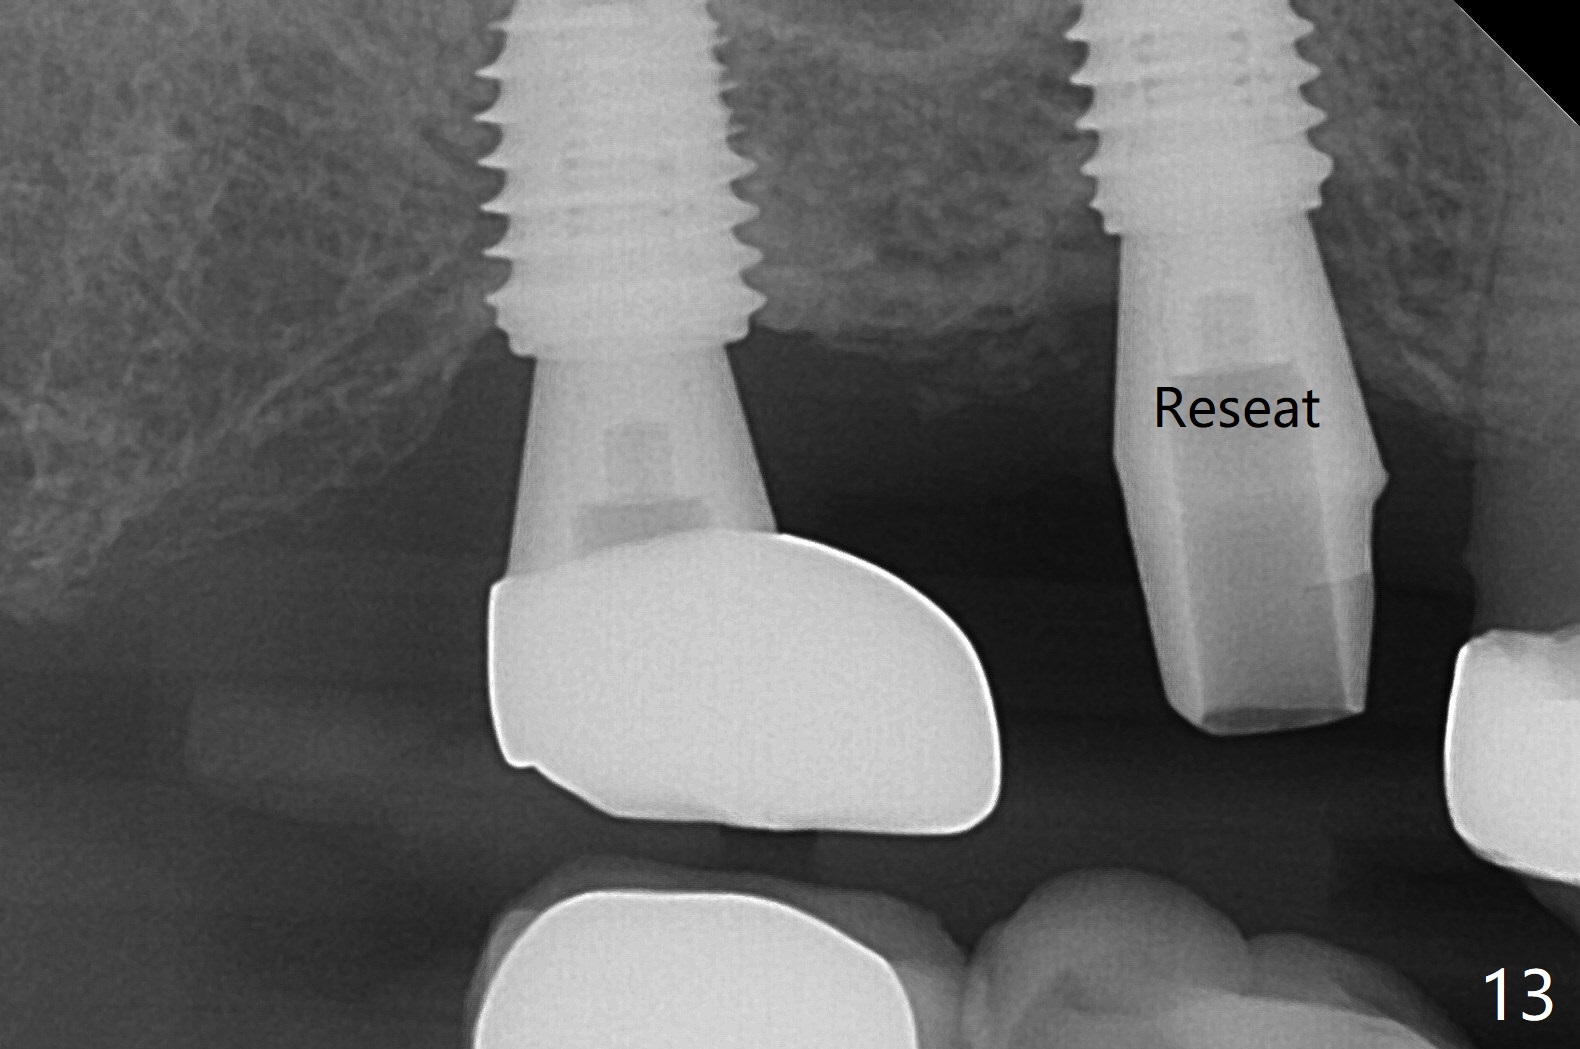

Sinus Lift Post Osteotomy

Osteotomy at the sites of #2 and 3 goes on as planned. Sinus lift using DIO 2.8 mm round bur with 6 and 7 mm stoppers (respectively) is carried on without certainty, because it is difficult to feel the stop through the osteotomy. The crest may be uneven or soft. It appears that the soft tissue landmark as a stop may be easier to identify. In fact a 3 mm IBS Magic Expander (an osteotome) was used for sinus lift at #3. The 2 implants are placed with 20 and 30 Ncm (Fig.1,2). Healing abutments are inserted. At 2-week follow-up, the patient reports "pain a few days earlier, took a pill of antibiotic, pain gone. UR metal is sharp". She does not take antibiotic regularly. Exam reveals that there is heavy plaque around #2,3 healing abutments. The buccal edge of #2 abutment is trimmed for comfort. Nearly 1 month postop, #3 healing abutment dislodges with buccal gingival erythema and edema with purulent discharge (Fig.3). Healing screw is placed at #3 with Amoxicillin and Chlorhexidine prescribed. One week later, the implant at #3 turns when the healing screw is retightened (Fig.4). After debridement, Vanilla graft is placed. There is no infection at #2 or 3 four months postop (Fig.5,6); the lingual gingiva is erythematous and edematous at #29 with mobility II (Fig.7 (vertical root fracture)). Uncover is conducted at the site of #3; there is no infection superficial 7.5 months postop (Fig.8). There is a large buccal defect upon incision with dark hemorrhage. In fact the bone density is low crestally (Fig.8 *). Bone graft is placed for the 2nd time. Eleven months later (1.5 years post implant placement), the bone regrows crestal (Fig.9 *). The crown at #3 is loose 1 year 5 months post cementation (Fig.10). After proximal trimming (Fig.11 *), the abutment at #3 is seated completely. After lab repair, crown oral cement, crown/abutment removal for excess cement removal, the crown/abutment cannot be torqued >25 Ncm (Fig.12, 30 Ncm). PA shows incomplete seating (Fig.12 <). Then the crown is sectioned so that the abutment has more freedom to be seated completely with pressure against the gingiva (the patient feels pain, Fig.13). Torque is 30 Ncm. After crown cementation, the abutment will not be removed for cement removal.